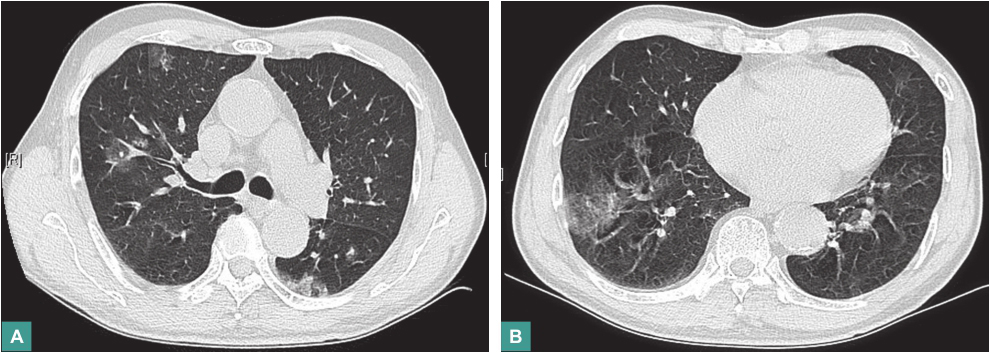

血常规:白细胞计数6.6×109/L,中性粒细胞比例57.2%,淋巴细胞比例29.7%,血红蛋白138g/L,血小板计数197×109/L。血生化全套指标正常。癌胚抗原(CEA)6.63ng/ml。血沉20mm/h。C反应蛋白8.05mg/L,免疫球蛋白E(IgE)1010.0IU/ml。T-SPOT阴性,自身抗体全套、ANCA全套指标均正常。血清半乳甘露聚糖试验(GM试验)及(1,3)-β-D葡聚糖试验(G试验)正常。肺吸虫、血吸虫等寄生虫抗体阴性。胸部CT示双肺多发磨玻璃影,病灶中见致密影(图1)。经抗细菌感染及抗结核治疗1个月,复查胸部CT示部分病灶吸收,部分增多、进展,有游走性特点。经支气管肺活检病理提示慢性炎症。支气管肺泡灌洗液找抗酸杆菌阴性。

图1 胸部CT表现

血常规大致正常,血清CEA稍增高,血清IgE明显升高,血清真菌感染检测阴性,自身抗体和ANCA检查均阴性,血清寄生虫抗体阴性。胸部CT示双肺多发磨玻璃影,病灶中见致密影。经支气管肺活检病理提示慢性炎症。

双肺多发磨玻璃影在肺部影像学上并不少见,多种疾病均可表现此类影像学改变,在确立诊断的过程中首先要进行以下方面的鉴别。

本例患者以咯血为主要表现,胸部CT提示双肺多发混合密度病灶,病灶中可见致密影,边缘见晕轮征,经外科胸腔镜下肺活检病理确诊为血管肉瘤,再结合患者无异常阳性体征,腹部及心脏彩超未见肺外原发灶,故可诊断原发性肺血管肉瘤。因此,对于病因不明的咯血、气促、双肺多发磨玻璃影伴中间致密影类似晕征病灶的病例,应考虑原发性肺血管肉瘤可能。尽早行组织病理检查有助于早期诊断及治疗,以改善预后。